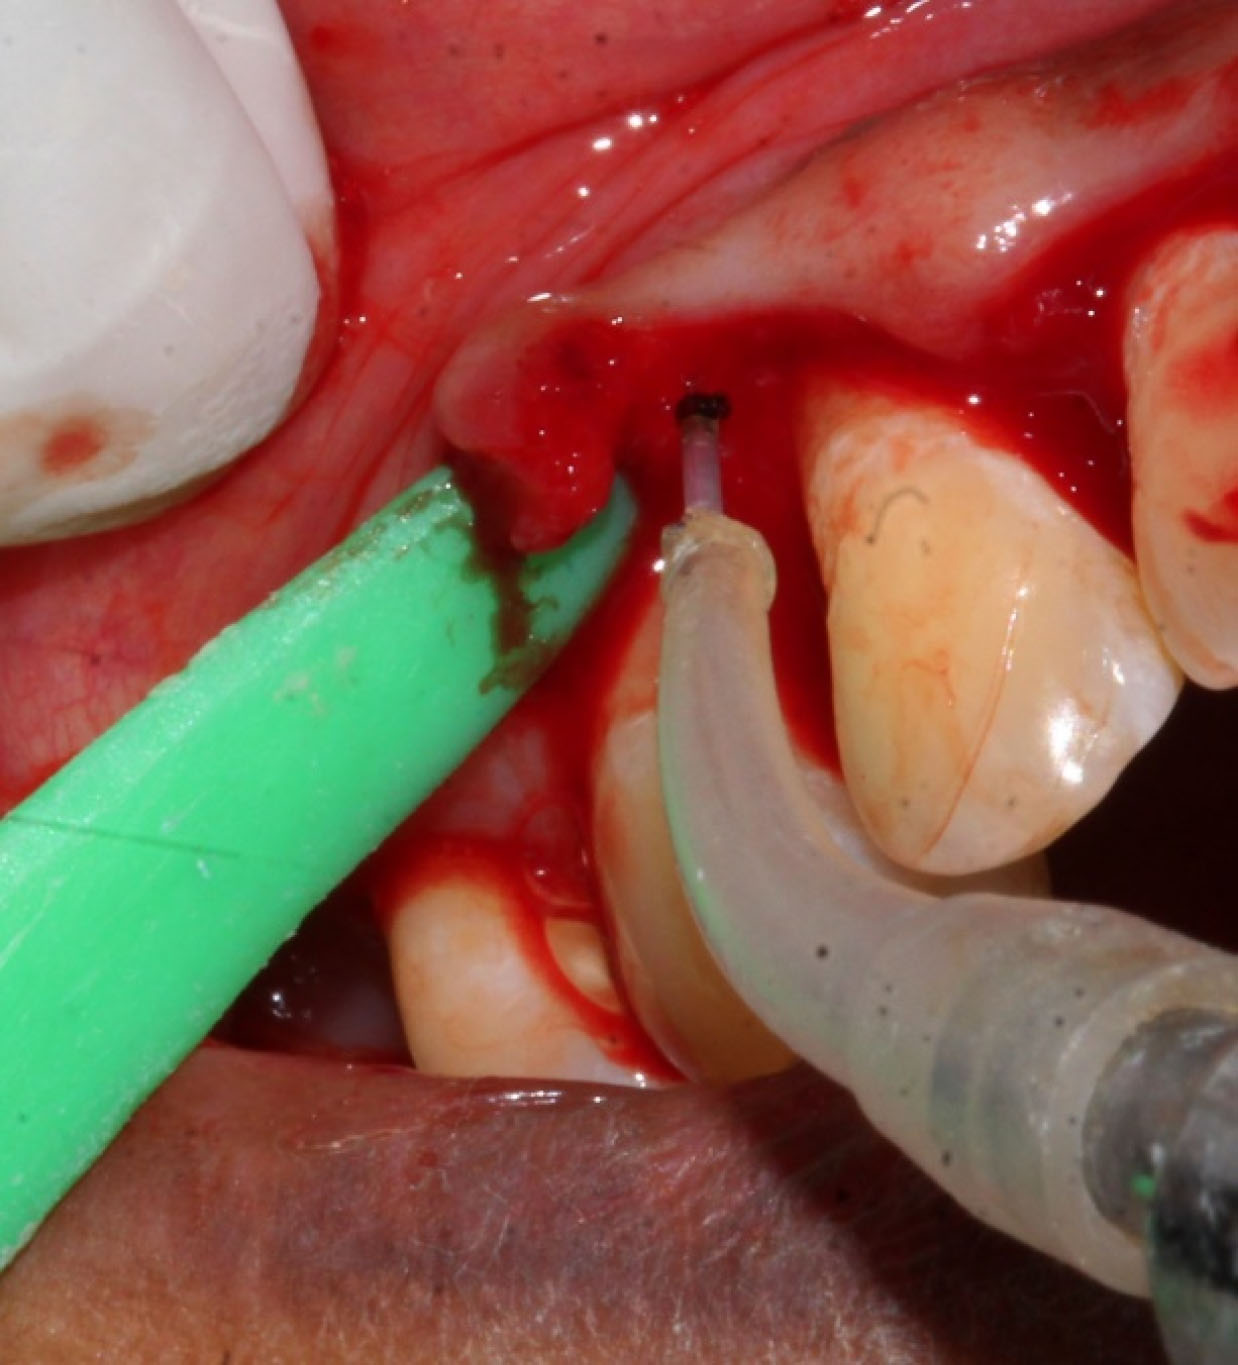

Control sites ( and ) were treated with MWF and sham application of DL therapy, whereas test sites underwent MWF and active DL application. In all the sites, the MWF was followed by SRP and elimination of granulation tissue using hand and power-driven instruments. Before each irradiation episode, a power meter (Fieldmaster, Coherent, Alburn, USA) was used, which allowed the adjustment and standardization of the amount of energy used. For test sites, a DL (wavelength = 940 nm, power = 1 W, tip diameter = 400 µm, power density = 796 W/cm2) was used in continuous mode to remove visible epithelium from the undersurface of the flap. The DL irradiation was carried out at a 45º angle to the soft tissue for 10 seconds from the coronal to apical aspect in parallel paths, followed by 30 seconds of interruption. The charing layer, which was produced due to laser application, was removed with moist gauze. A second laser application (LLLT) was carried out on all the surfaces of the flap (under and outer, exposed bone, and exposed root structures) in continuous mode at 0.1 W, adding up to a total dose of 4 J/cm2 per surface (). The flaps were sutured with 3-0 black silk sutures. Ibuprofen with a 200-mg dose was prescribed every eight hours for five days for pain control. Furthermore, patients were requested to avoid brushing in the treated area for two weeks. They resumed full oral hygiene and function after two weeks.

Figure 4. Test group de-epithelization with diode laser.